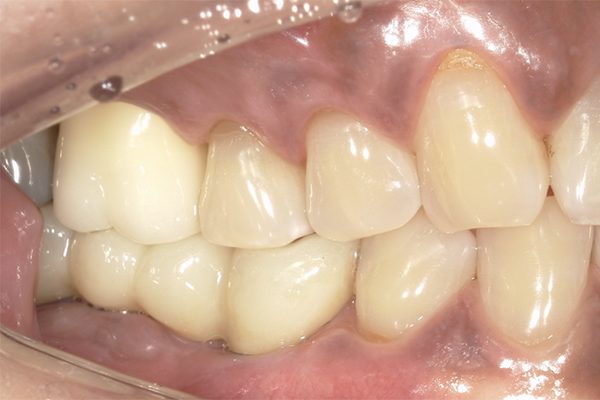

| 主訴 | 奥歯で噛めない、顎が痛い |

|---|---|

| 治療内容 | 奥歯のインプラント治療、前歯・奥歯の被せ物治療 |

| 治療期間 | 6ヶ月 |

| 治療費 | 350万円 |

| 治療リスク | 被せ物をつけた初期の段階で歯がしみることがある(時間とともに改善する) インプラント治療後に3日程度痛みと腫れを伴うことがある |